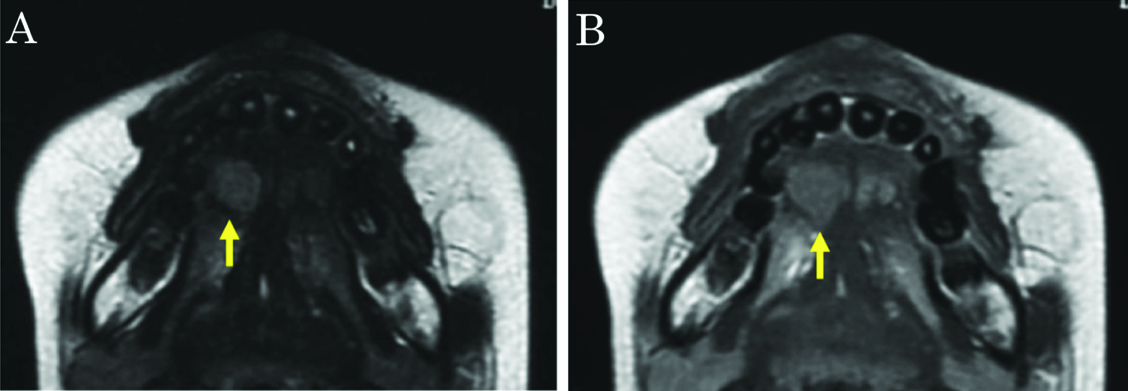

Ultrasonography revealed a rounded mass in the right side of the tongue, with irregular, unsharp borders. Ultrasonography demonstrated a predominantly hypoechoic appearance, with some hyperechoic foci [Table/Fig-2]. Magnetic resonance imaging (MRI) demonstrated a mass in the right side of the tongue, with slightly elevated signal intensity on T2-weighted imaging, and weak enhancement on gadolinium-enhanced T1-weighted imaging [Table/Fig-3a,b]. Laboratory analyses showed: white cell count, 3,000/μl; lactate dehydrogenase, 188 U/l; serum alpha-fetoprotein (AFP), 182 ng/ml; serum IgG, 480 mg/dl; serum IgM, 571 mg/dl; and serum IgA, 4 mg/dl. The tumour was initially diagnosed clinically as salivary gland tumour, such as pleomorphic adenoma. However, we considered that the tumour might represent malignant lymphoma, because the patient had already been diagnosed with AT.

A) T2-weighted imaging. The mass showed slightly elevated signal intensity. B) Gadolinium-enhanced T1-weighted imaging. The mass shows weak enhancement